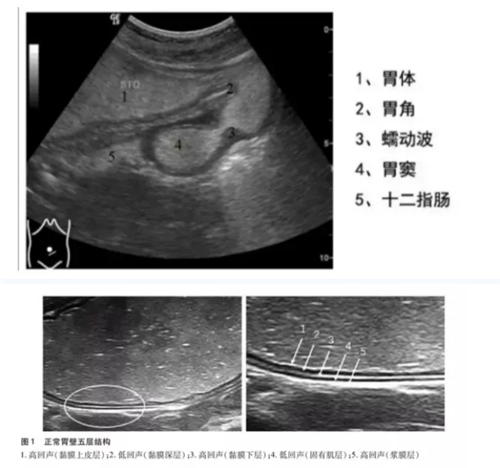

正常胃壁声像图:

胃肠充盈超声造影检查,它是通过一种造影剂充盈胃肠腔,该类造影剂充盈胃肠腔后在声像图上显示类似于实质性组织的回声,消除了胃腔内的气体及粘液干扰,和胃肠壁及肝、胆、脾、胰之间产生明显的对比效应,清晰地显示胃肠壁的层次结构,从而使胃肠内腔产生良好的声学造影效果。